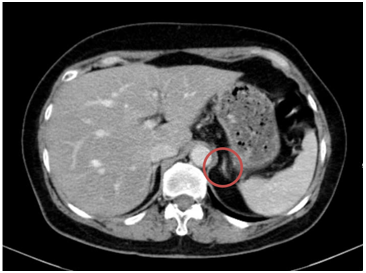

-  Chụp cắt lớp vi tính bụng: Theo dõi dày khu trú tuyến thượng thận trái tạo nốt đường kính khoảng 9mm

Hình 3. Hình ảnh chụp CT bụng trước điều trị: Nốt tuyến thượng thận trái

- Chụp cắt lớp vi tính bụng: Theo dõi dày khu trú tuyến thượng thận trái tạo nốt đường kính khoảng 9mm (không thay đổi)

Hình 10. Hình ảnh chụp CT bụng sau điều trị: Nốt tuyến thượng thận trái